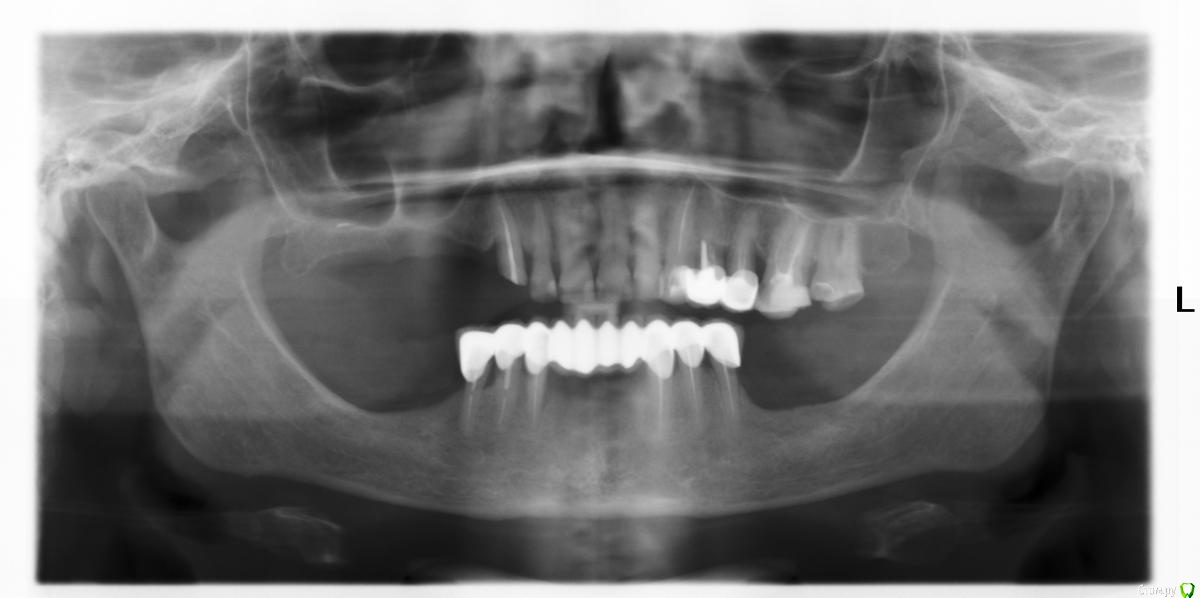

Bratok Опубликовано 26 июня, 2015 Поделиться Опубликовано 26 июня, 2015 (изменено) Коллеги случай не простой, помогите с планом лечения..Пациента интересуют верхние зубы. Внизу есть съемный с ацеталовыми кламерами типа квадротти. Вот как я вижу ее реабилитацию:Верхние зубы 2.4,2.5,2.6 диагностич.преп и либо ревизия либо удаление.У пациента еще запрос на эстетику фронтальных зубов, от металлокерамики отказывается..E.max дорого.. Может преттау?Что бы вы сделали с 1.3, удаление ? Имплантация не рассматривается..(она тут вообще возможна? Особенно нижние) После ревизии и покрытия зубов коронками (все верхние зубы)Бюгельный протез: как на фото с рисунком.. Либо дуга будет идти по всем зубам, не через небо Изменено 26 июня, 2015 пользователем Bratok Ссылка на комментарий

Bratok Опубликовано 27 июня, 2015 Автор Поделиться Опубликовано 27 июня, 2015 Клык здесь был под коронкой (1.3 зуб)..очень агрессивный преп.. Хотя феррул есть..но смущает ситуация на оптг.. Ссылка на комментарий

Ivanov_dentist Опубликовано 27 июня, 2015 Поделиться Опубликовано 27 июня, 2015 Выдвину на суд коллег свой план:1. Удалить 1.3, 2.4, 2.52. Определение ЦС - воск, терапевтическая подготовка3. 1.2-2.2 - Е.макс или диоксид, 1.3- 2.6,2.7 - МК с балкой 4 Бюгельный протез на ВЧ с элементом пелота в области 1.2 PS это только мое предложение, выслушаю советы если есть ошибки моего плана. Ссылка на комментарий

Ivanov_dentist Опубликовано 27 июня, 2015 Поделиться Опубликовано 27 июня, 2015 Напрягает атрофия кости именно в области протезированных зубов на верхней челюсти. Ссылка на комментарий

Bratok Опубликовано 29 июня, 2015 Автор Поделиться Опубликовано 29 июня, 2015 состояние костной ткание не позволяет Ссылка на комментарий